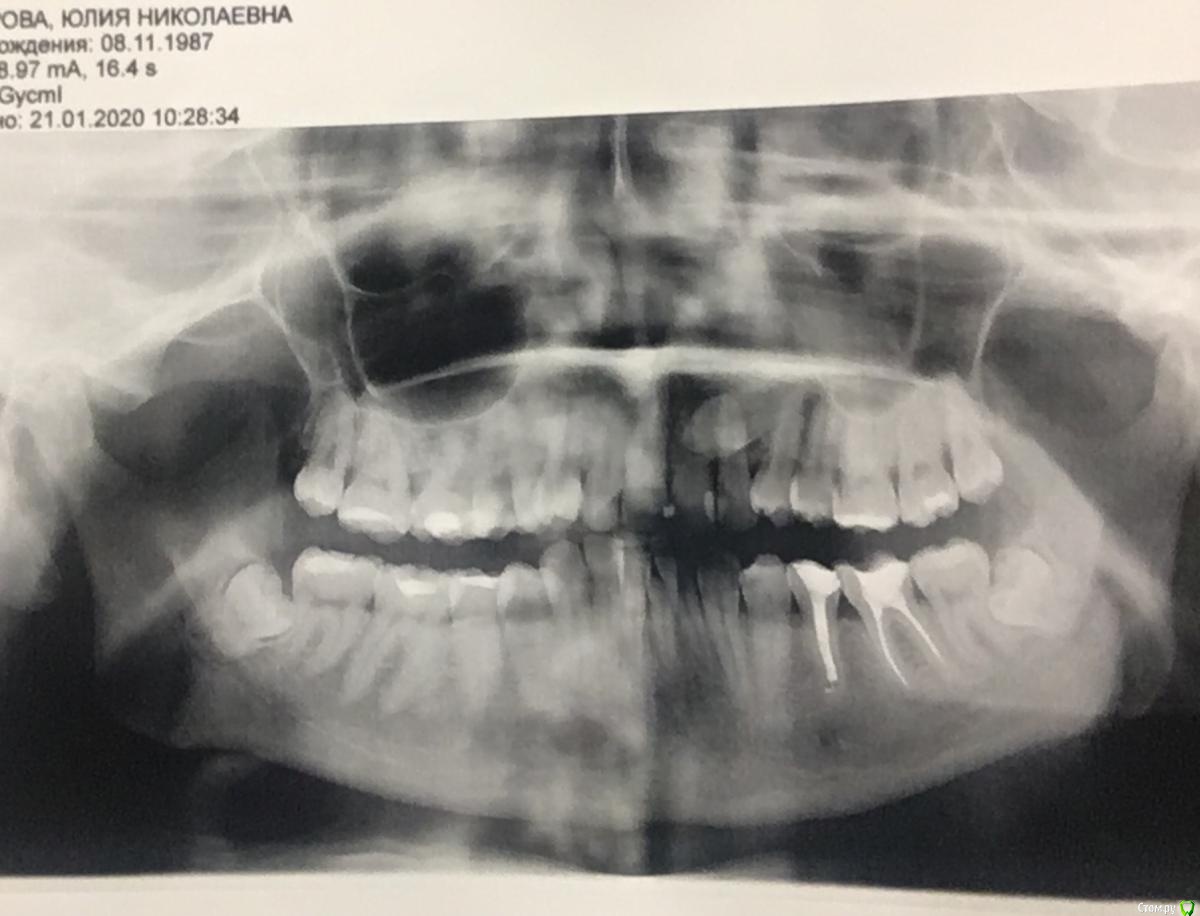

Уважаемые доктора, помогите пожалуйста! В моем городе только один врач-ортодонт, а выехать куда-либо на консультацию с другим специалистом, к сожалению, пока возможности не имею, а ситуация сложная. Суть вопроса такова. У меня есть ретинированный зуб, клык. В детстве я носила брекиты, лечение длилось три года. Тогда клык мне убирать не стали, просто выровняли зубной ряд, в результате на верхней челюсти сместился центр, а нижний ряд выпрямили. Ретейнеры не установили, в результате сейчас такая ситуация (фото). Спустя 15 лет решилась снова заняться решением своей проблемы, так как просто эстетикой это уже не ограничивается. Обратилась к тому же доктору, так как, повторюсь, доктор у нас один и работает с давних пор. Что она предлагает: 1) убрать ретинированный зуб 2) удаление одного зуба с нижней челюсти 3) установка брекит-системы и выравнивание. Прикус у меня глубокий. Дело в том, что при выравнивании зубного ряда сверху смещение центра ещё более усугубится ( я так предполагаю). И при удалении зуба с нижнего ряда тоже получится смещение. Хотелось бы узнать мнение, неужели нет альтернативных вариантов? Очень не хочется в результате получить смещённую челюсть((((. Вот так удалю зуб снизу по рекомендации доктора, а, как говорится, зуб не волос, новый не вырастет. Прошу, помогите пожалуйста(((.

Спасибо Вам огромное, что подсказали, небезразличным людям добро возвращается в стократном размере! А для меня это целая жизнь, с желанием жить ее без комплексов и в здравии)))Прикладываю фото!)